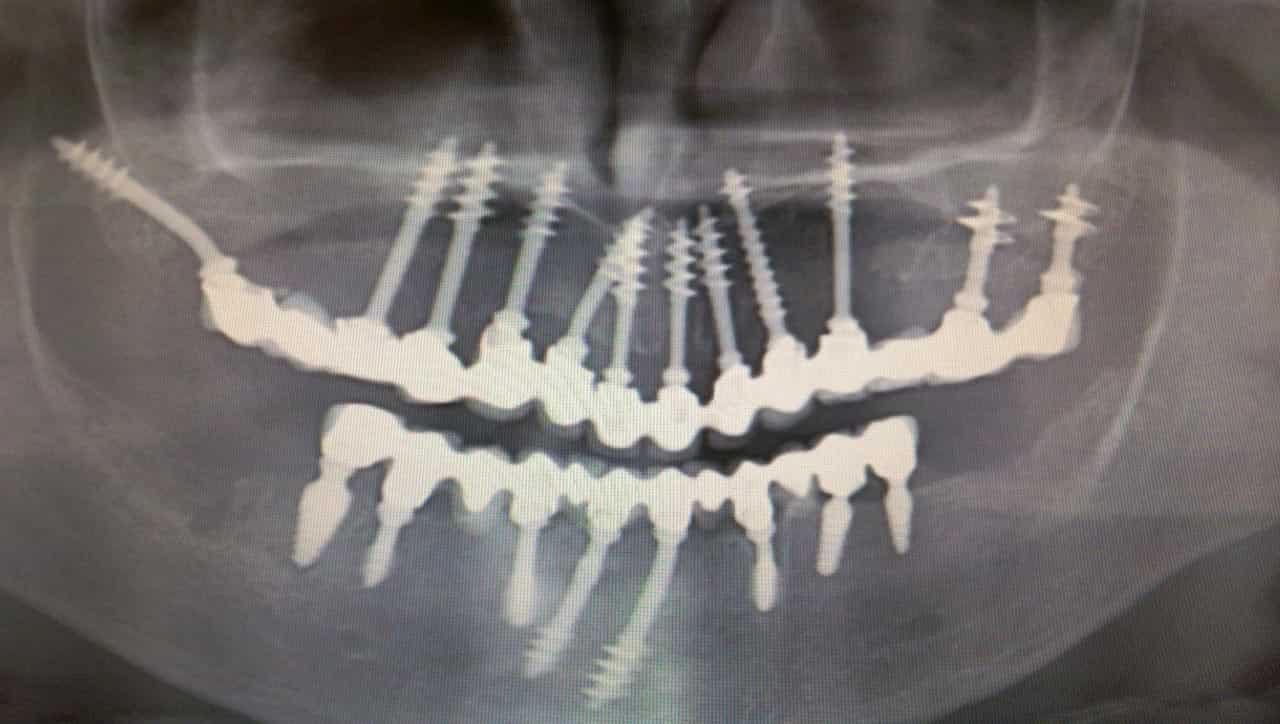

fog implantátum Budapesten

A fog implantátum Budapesten garanciával érhető el

A fogászati beavatkozások hazánkban nagy fejlődésen mentek keresztül. Ezt mi sem bizonyítja, hogy országszerte végeznek beültetéseket. A fog implantátum Budapesten minden esetben szakértelemmel készül, szóval hosszútávon megállja a helyét a mindennapokban. Ez a kisebb műtét teljes mértékben fájdalommentes, szóval nem szükséges érzéstelenítőt alkalmazni.

A páciens az egészből nem érez semmit. A beavatkozás után jelentkező kisebb fájdalom 1-2 napon belül elmúlik. Ha ezután kicsit érzékeny a fogíny, még nem kell megijedni. A szakember részletesen elmagyaráz mindent Önnek ezzel kapcsolatban. A fog implantátum Budapesten több rendelőben kivitelezhető. Választhatja azt a klinikát, amelyik a legközelebb helyezkedik el az otthonához, így nem kell órák hosszat utaznia.

Mindenhol speciális felszereléssel dolgoznak, hiszen ez a követelmény. A rendelők rendkívül hangulatosan vannak berendezve, ami nagyon fontos. A fog implantátum Budapesten garanciával van ellátva. Az időtartam klinikánként változó. Ez a dolog még nagyobb elégedettséget mutat az érintettek részéről.